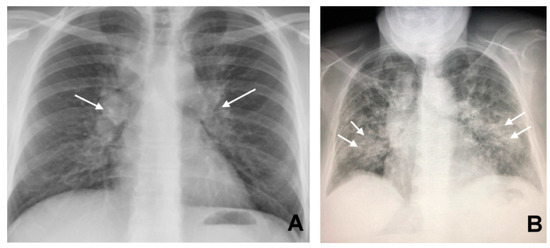

2. Sarcoidosis, the Chameleon Disease

3. CT in Pulmonary Sarcoidosis, Imaging Findings and Classification